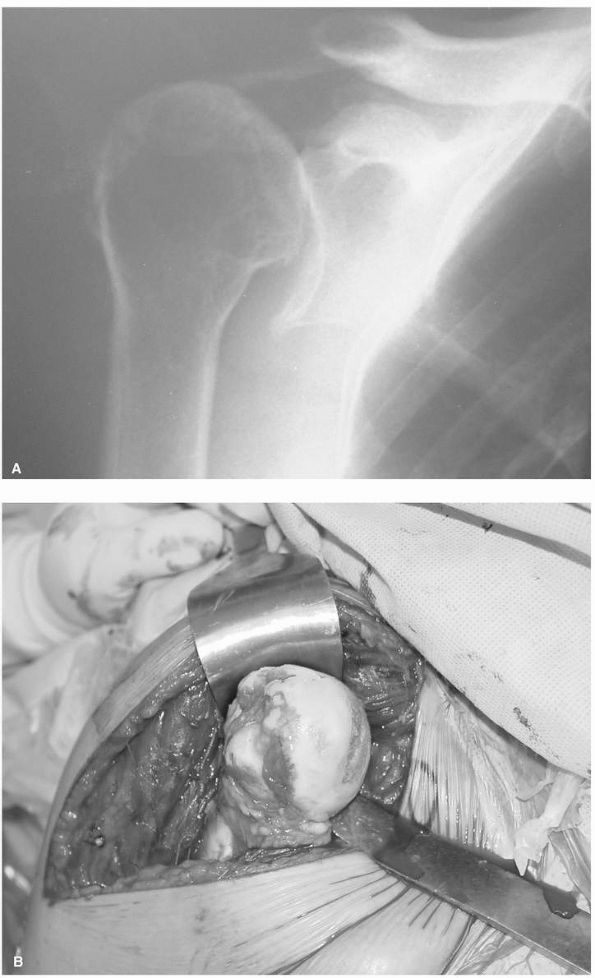

pathological process. Degenerative disease manifests itself similarly

to other joints with narrowing of the joint space, subchondral cysts

and sclerosis, and osteophyte formation (Figure 12-2).

In contrast, osteolysis of the distal clavicle may demonstrate relative

osteopenia, widening or tapering of the distal clavicle, and expansion

of the joint space (Figure 12-3).